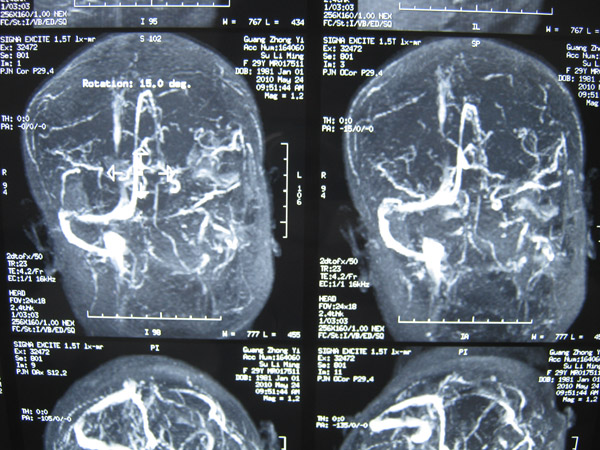

2011年5月1日,覃某顺产1名女婴后出现发作性意识障碍,伴双目上视,伴牙关紧闭、口吐白沫、四肢抽搐、二便失禁,醒后伴头晕、四肢乏力、左侧肢体麻木等不适症状,遂到当地医院就诊。在其住院过程中出现意识障碍伴左侧肢体活动障碍、左下肢肿胀等症状,在进行头颅MRI+MRA等检查后,覃某被当地医院诊断为“颅内静脉窦血栓形成并伴脑皮质出血、症状性癫痫、左下肢静脉血栓形成”。

上矢状窦血栓形成1

上矢状窦血栓形成2